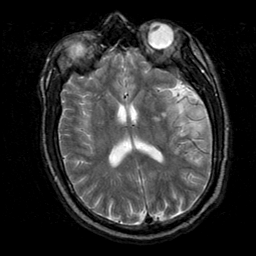

Subacute Stroke, overlay -- Slice #14

[Home][Help][Clinical] Slice 14